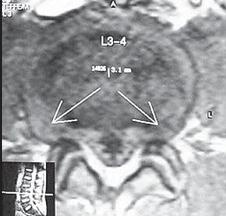

МРТ № 11

МРТ № 12

На МРТ № 11 наблюдается парамедианная грыжа межпозвонкового диска, которая как бы обхватывает с двух сторон спинной мозг

На МРТ № 12 наблюдается медианная (срединная) грыжа межпозвонкового диска, которая часто протекает безсимптомно и может достигать больших размеров